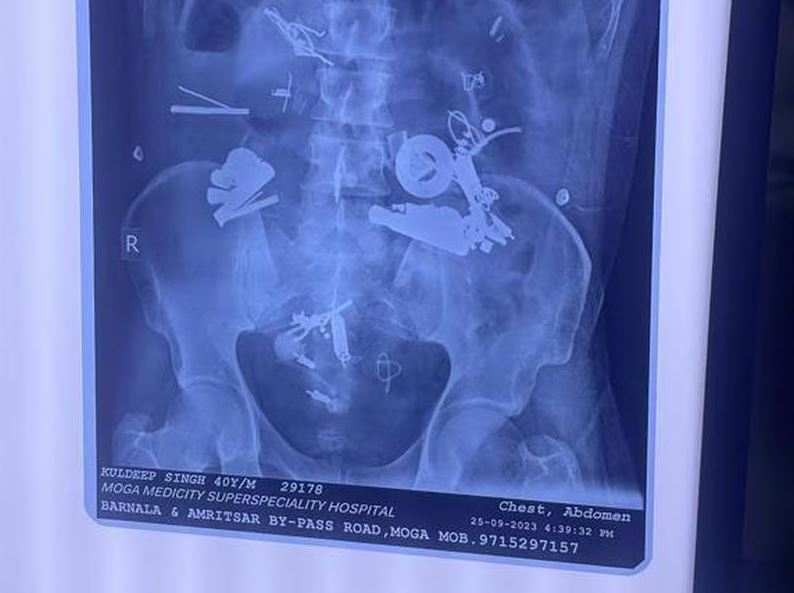

فرارو- پزشکان در ایالت پنجاب در شمال هند پس از کشف و خارج کردن سمعک، دستبند، پیچ و مهره و سنجاق قفلی در میان ۱۵۰ شئ خارجی در معده بیمار تحت عمل جراحی قرار گرفته بهت زده شدند. این مرد ۴۰ سال روز دوشنبه هفته گذشته با ابراز گلایه از درد شدید معده و حات تهوع در بیمارستان مدیسیتی در ناحیه موگا در ایالات پنجاب در هندوستان بستری شد. پزشکان با بررسی تصاویر گرفته شده با استفاده از اشعه ایکس متوجه شدند اشیاء فلزی در داخل بدن آن بیمار وجود دارند. آنان بلافاصله عمل جراحی را آغاز کرده و در جریان عمل جراحی سه ساعته سمعک، دستبند، پیچ و مهره، سیم، قفل، دکمه و سنجاق قفلی از شکم او بیرون آوردند. این مرد روز پنجشنبه پس از عمل جراحی بر اثر سپسیس* جان اش را از دست داد.

به گزارش فرارو به نقل از نشنال امارات، دکتر "اجمر کالرا" مدیر بیمارستان گفت:"زمانی که گزارش‌های اشعه ایکس را دریافت کردیم بهت زده شده بودیم. محموعه‌ای از اجسام خارجی در شکم او وجود داشتند. پس از جراحی ما ۱۵۰ قلم شئ از جمله دستبند، زیپ، میخ و پیچ و مهره پیدا کردیم. بیمار نزدیک به یک هفته درد داشت. ما از دستگاه تنفس مصنوعی برایش استفاده کردیم، اما نتوانستیم وی را نجات دهیم. او دچار تورم ناحیه شکم شده بود که در نهایت باعث سوراخ شدن شکم اش و در نهایت سپسیس شد و به همین خاطر جان اش را از دست داد".